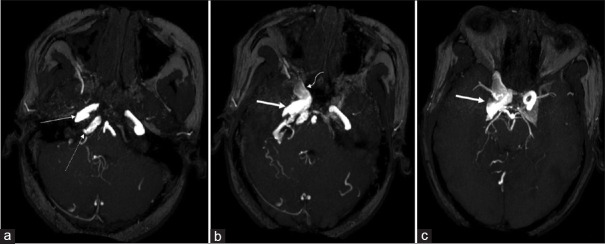

A 28-year-old Male with Complaints of Redness in the Right Eye with Proptosis: Direct Carotid-cavernous Fistula.

一位28岁男性,主诉右眼发红并突出:直接颈动脉海绵状瘘。